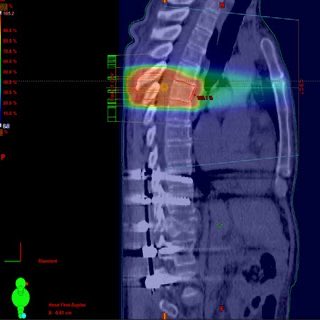

-الاعراض الناتجه عن انتشار المرض للعمود الفقري وتأثيره على الحبل الشوكي او جذور الاعصاب (الم، تنميل، شلل، التبول والتبرز اللا ارادي)